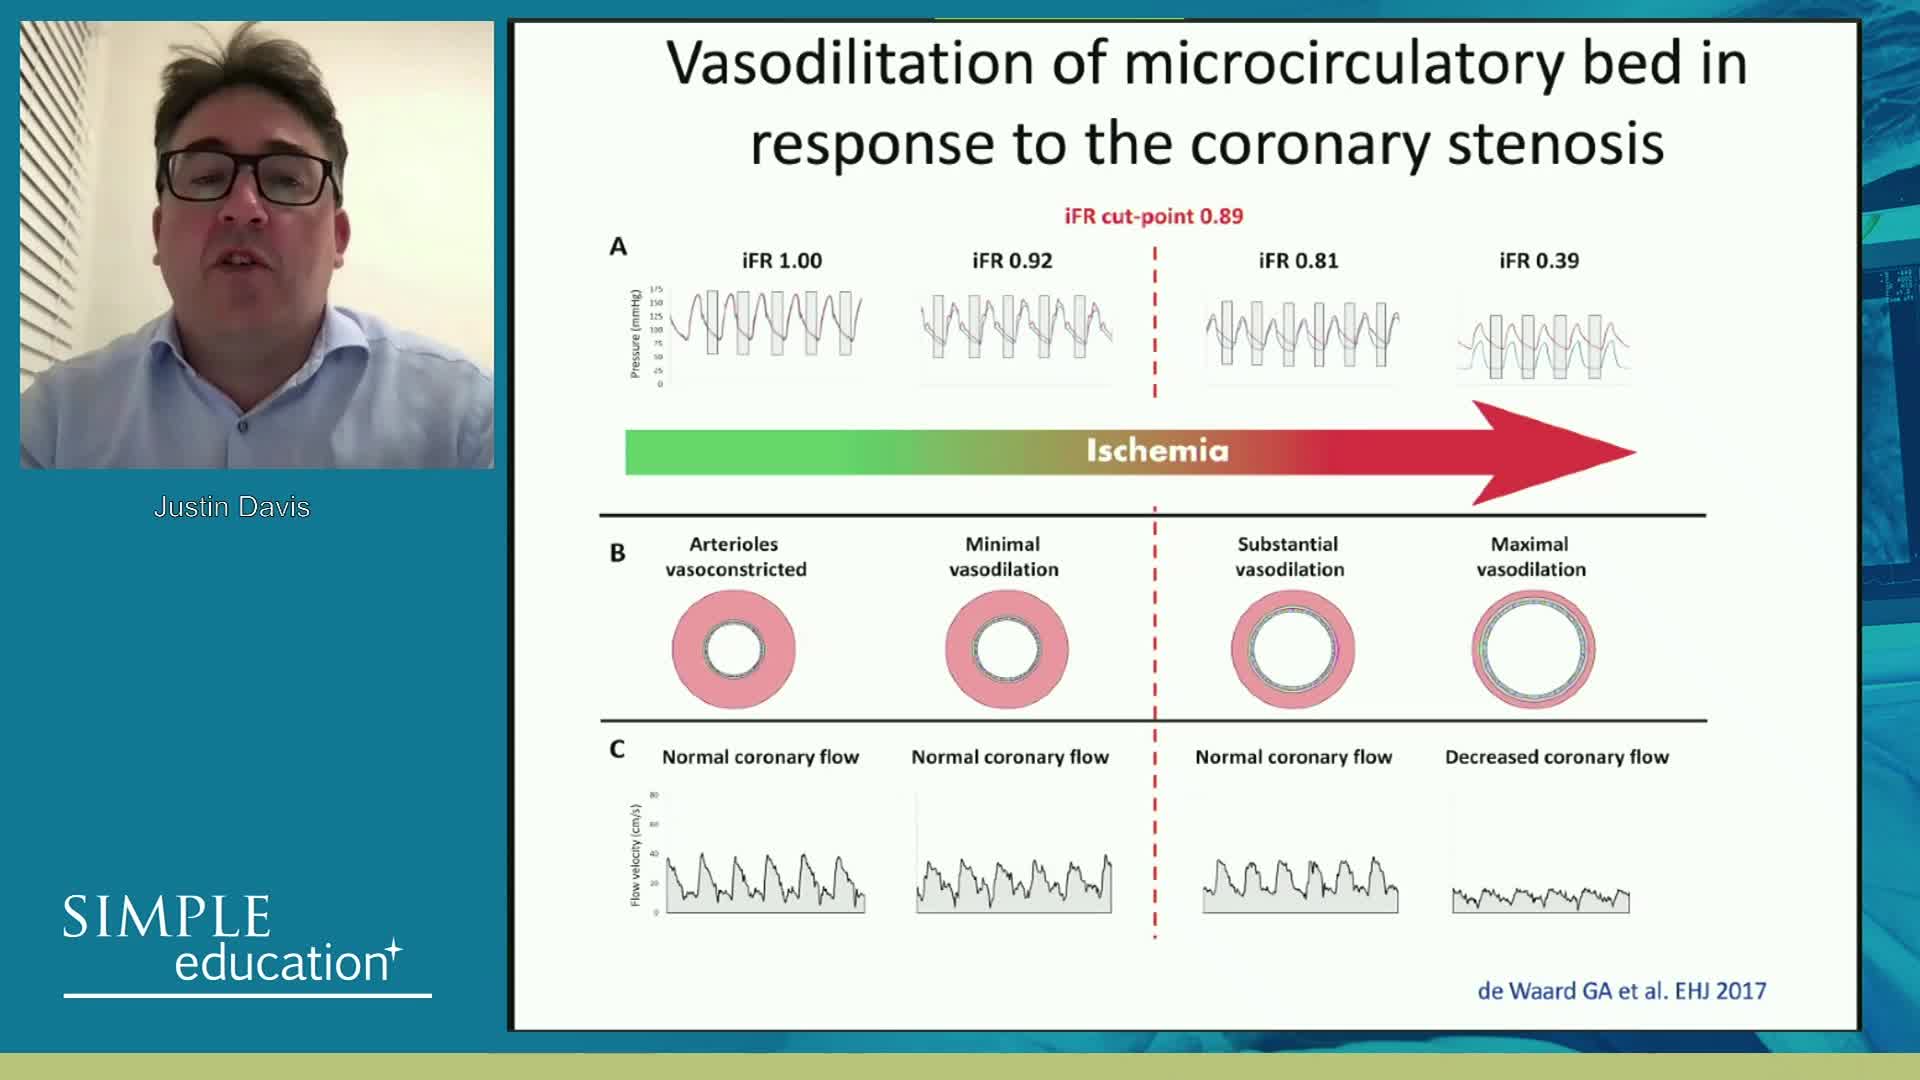

Understanding mechanisms of regulation of resting and hyperaemic blood flow, across single and serial stenoses

Why is the physiology negative? Integration of the coronary microcirculation to decision-making